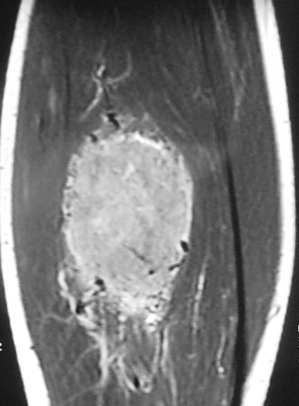

Radiographic imaging is used to help form a diagnosis. These include MRI, CT and Bone Scans.

An example of an MRI is shown.